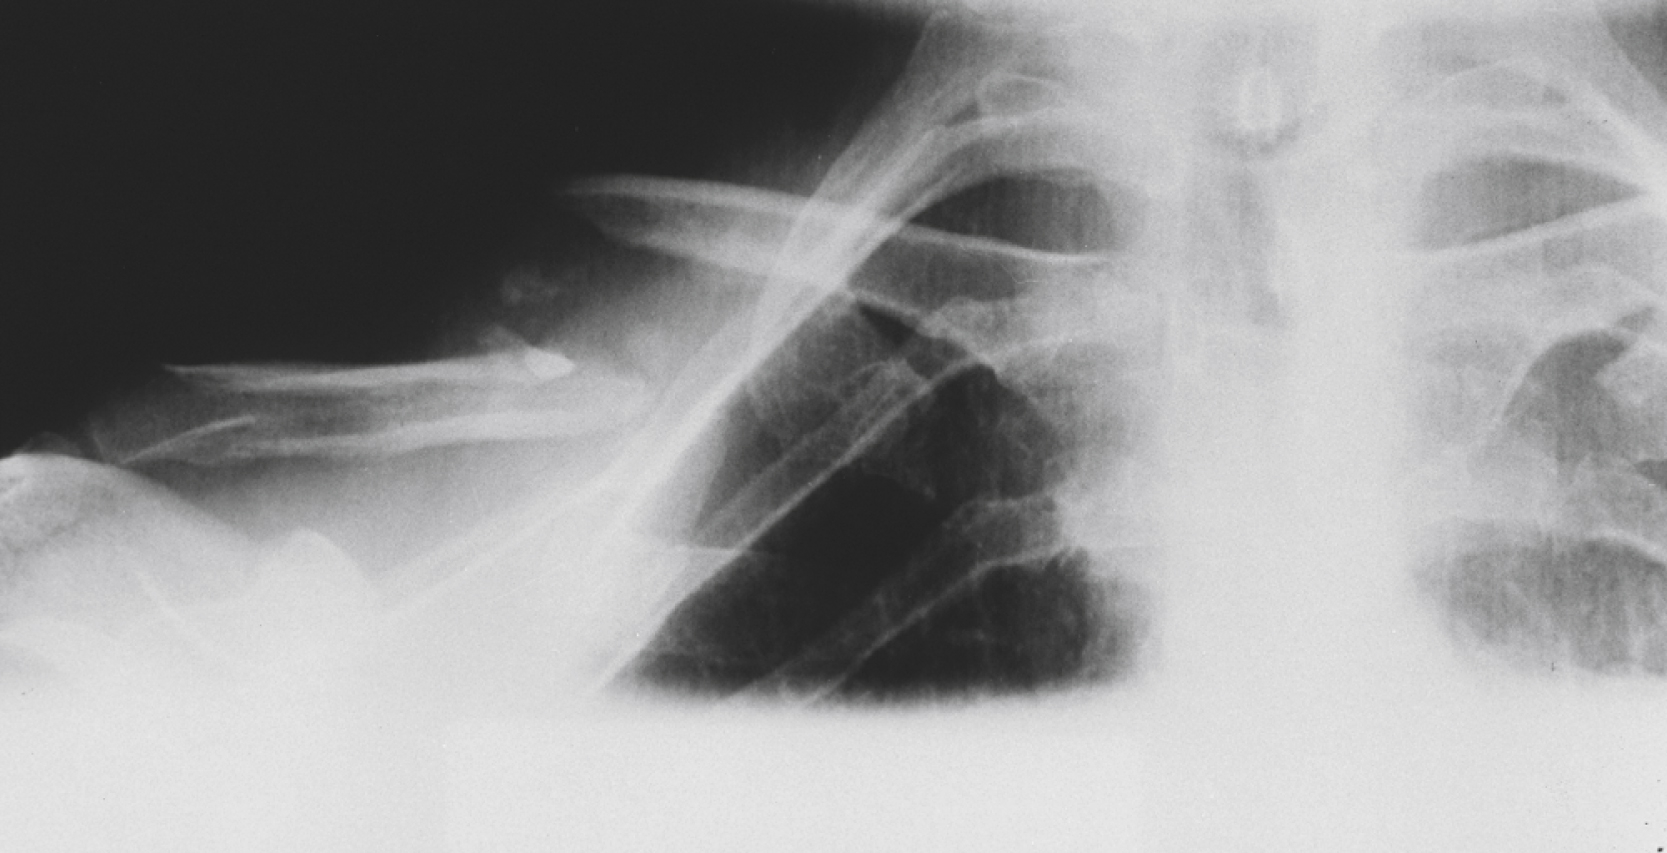

Fractures of the scapula are rare, accounting for approximately 1% of all shoulder fractures and caused by high-energy trauma, such as high-speed MVCs and falls from heights. Scapular fractures rarely require management but are associated with major injury (75% to 98%), specifically injuries to the ipsilateral lung, chest wall, and shoulder girdle complex. The most common associated orthopedic injuries are fractures of the ribs, proximal humerus, and clavicle. Associated lung injuries, including pneumothorax, hemothorax, and pulmonary contusion, usually occur acutely, but may manifest up to 2 to 3 days after the initial injury. Associated injuries of the head, spinal cord, brachial plexus, and subclavian or axillary vessels are less common.

Scapular fractures are divided into two main types: extra-articular (neck [ Fig. 45.11 ], body, acromion process, coracoid process, spine) and intra-articular (with partial or total glenoid involvement).

Extra-Articular Fracture Involving the Neck of the Scapula.

Note the associated midclavicular fracture.

Diagnostic testing

Radiology

The three-view trauma shoulder series will reveal most scapular fractures, as will careful examination of the scapula on the trauma chest radiograph. An os acromiale (unfused acromial process epiphysis) is present in 3% of the population, will not be tender to examination, and should not be confused with an acromion fracture. A comparison film can be useful, because the abnormality is present bilaterally in 60% of cases. Although additional dedicated scapula views can be obtained in the ED, the presence and the extent of scapular injury is best determined by CT scan. In the event that a trauma chest CT scan has been obtained to search for associated injuries, a three-dimensional reconstruction of the scapula should be requested to define the nature and extent of the injury.